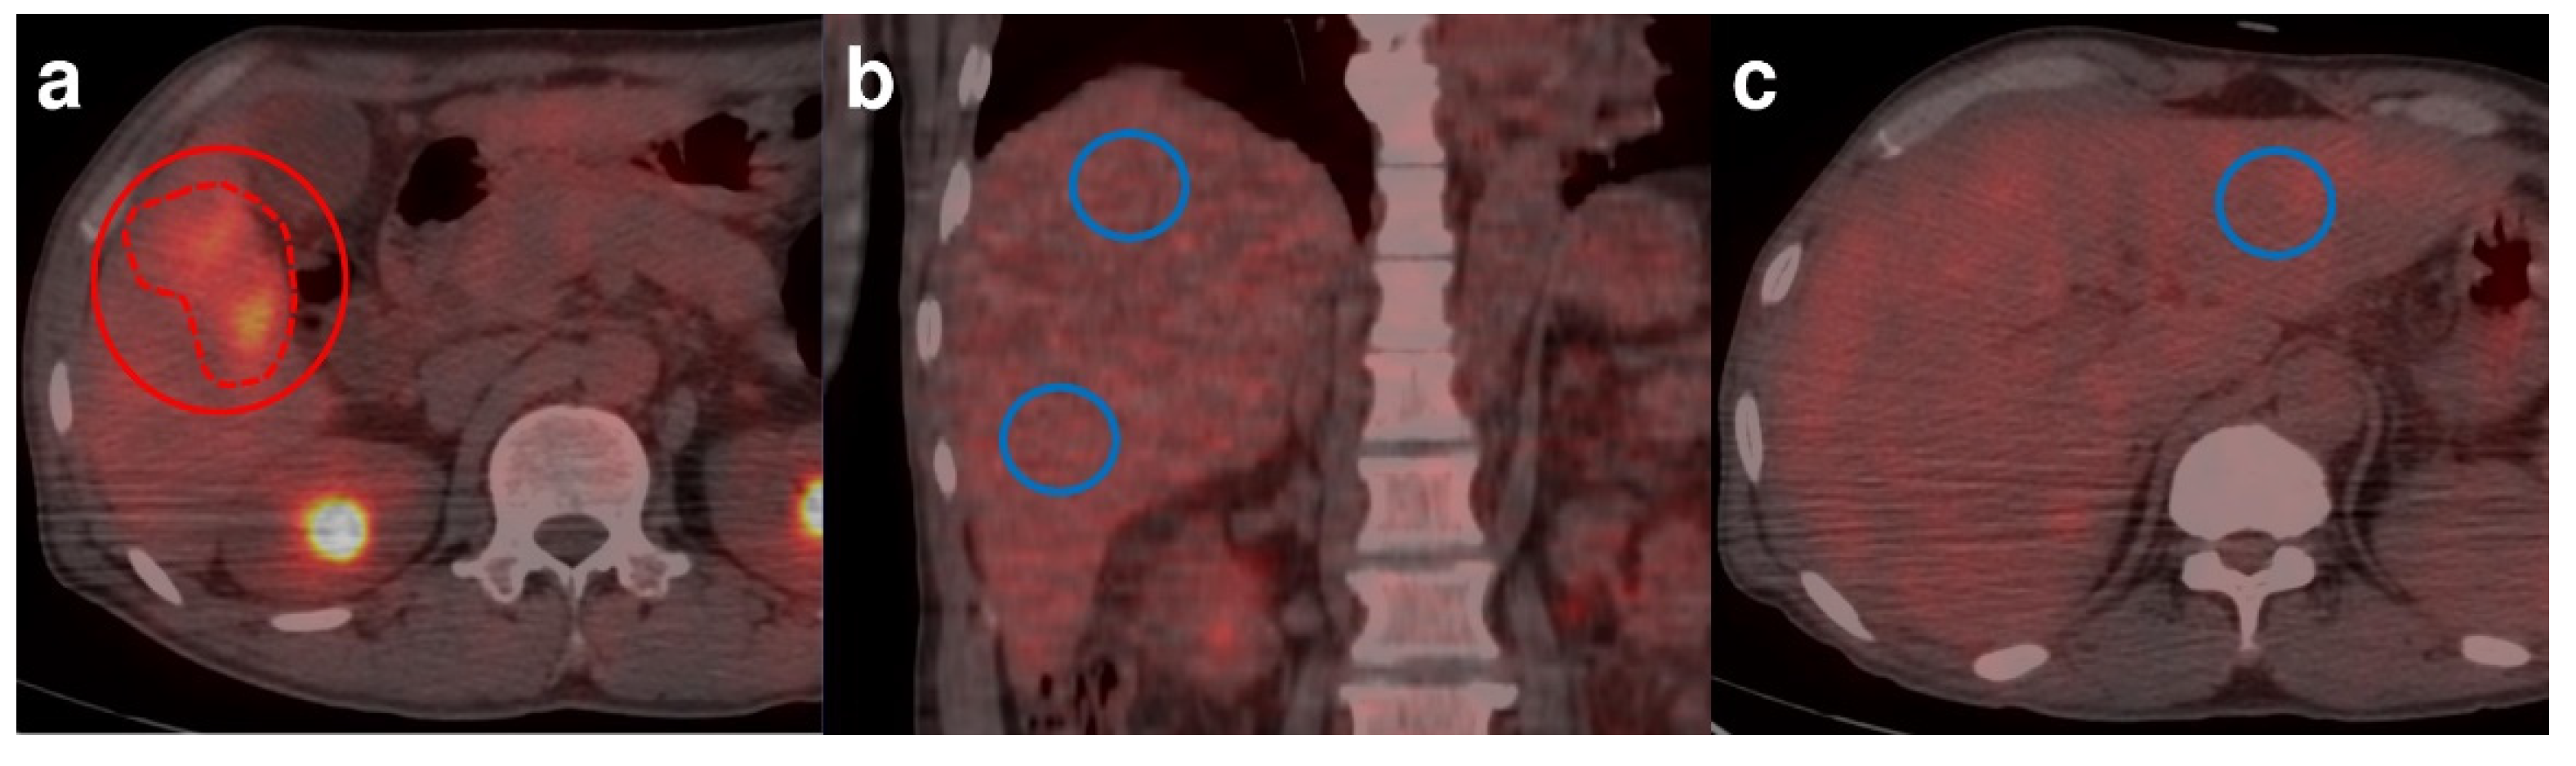

2.3. 18F-FDG PET/CT Interpretation and Image Analysis